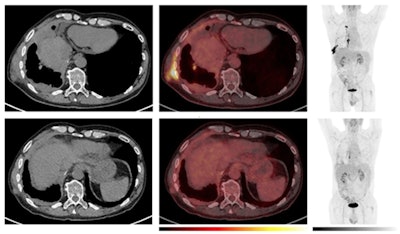

Example of a patient with a decline in metabolic tumor volume (MTV) and F-18 FDG uptake as early as the week-five PET scan, which was followed by a long-term objective tumor response. Comparative imaging from baseline (top row) and week five (bottom row). To the left, axial CT images; in the middle, axial PET/CT images; and to the right, the maximum intensity projection (MIP). The PET images are observed within a 0-10 SUV window. The patient was classified as having stable disease at the first CT response assessment, before developing partial response at the week-12 CT scan according to the modified Response Criteria in Solid Tumours (mRECIST) and immune RECIST. While the patient had stable disease at the week-5 CT scan, PET/CT already showed a reduction in MTV and a decline in [F-18] FDG uptake in the tumor. The treatment was discontinued after seven months due to intolerable toxicity. The patient is still under follow-up 20 months after the start of the treatment. All figures courtesy of Dr. Solfrid Thunold et al and EJNMMI.